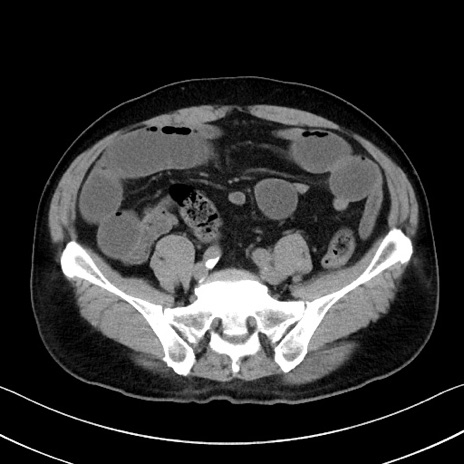

症例35(横断像)

【症例】70歳代 男性

【主訴】腹部膨満、嘔吐

【現病歴】昨日より腹部膨満感出現。本日増悪し、仙痛出現。嘔吐あり、受診。

【既往歴】糖尿病、胆摘後

【身体所見】BP 149/80mmHg、HR 74/min、BT 35.9℃、腹部:膨満、軟、圧痛なし。腸雑音減弱あり。上腹部正中切開瘢痕あり。

【データ】WBC 13500、CRP 1.72